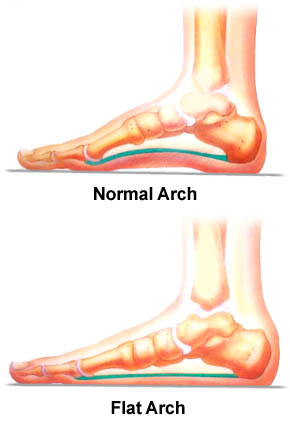

INCREASE OF Q ANGLE CAN CAUSE CHONDROMALACIA PATELLA AND ANTERIOR KNEE PAIN AND OVER PRONATED FOOT